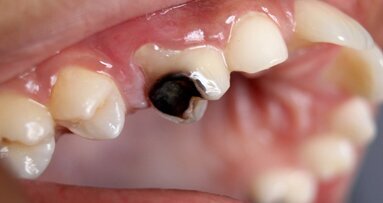

Japanese scientists are on the brink of a dental revolution with their new drug that has sparked hope for growing teeth. Clinical trials are set to begin for Toregem Biopharma’s drug that has successfully grown new teeth in animal test subjects.

In a remarkable breakthrough that could revolutionize dental healthcare, a team of Japanese scientists from the innovative pharmaceutical startup Toregem Biopharma are on the verge of introducing a groundbreaking drug that may enable the growth of new teeth. The development has garnered widespread attention and has raised hopes for individuals suffering from tooth-related issues.

The foundation of their groundbreaking discovery hinges on a specific gene found in mice, known as USAG-1, which profoundly influences the development of their teeth. The scientists uncovered the gene's dual role, capable of either promoting or impeding dental growth. The pivotal idea that emerged was to create a "neutralizing antibody medicine" designed to effectively block the adverse effects of the USAG-1 gene, thereby unlocking the potential for tooth regeneration.

The upcoming phase in this extraordinary odyssey is nothing short of monumental – human trials. The Toregem Biopharma team is poised to commence clinical trials as early as July 2024, marking a critical juncture in their quest to make transformative medicine available to the masses. Their ambitious goal is to bring the drug to market by 2030, ushering in an era where individuals with dental issues can regain their smiles.

However, this story is not solely about adults seeking to replace lost teeth; it carries a message of hope for a select group of children. Those afflicted by anodontia, a rare genetic disorder that results in the absence of six or more baby and/or adult teeth, may find solace in the fact that a clinical trial tailored to their specific needs is slated to commence in 2025.

In conclusion, the chronicle of Toregem Biopharma's relentless pursuit of dental innovation is nothing short of a scientific marvel. The prospect of regrowing teeth has shifted from the realm of dreams to the brink of reality, and it is a testament to the ingenuity and dedication of these visionary scientists. As we stand at the precipice of a dental revolution, the ability to regrow one's teeth may soon be within our grasp.